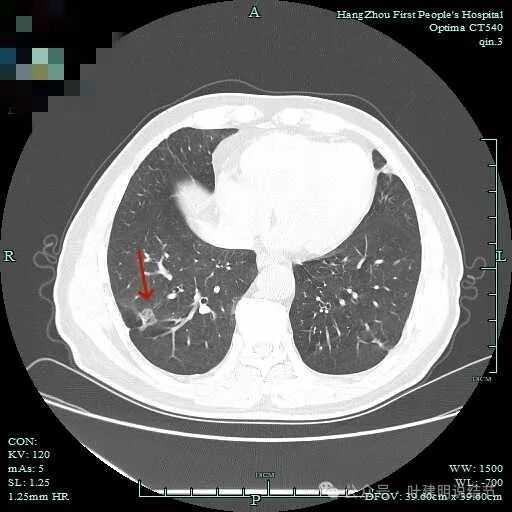

病仍明显,从上到下,觉得应该是成片的。

表面不平毛刺,实性密度为主。

微小血管有,但无异常增粗。

病灶实性,边缘不光滑。

实性密度,片状,条状。

病灶实性,缺乏膨胀性。

上图呈结节状,表面不平,有少许磨玻璃成分。

结节状,密度高,边缘欠光滑。

与脊柱之间有间隙,表面有细毛刺。

表面不平,似有细支气管截断征。

边缘不平毛糙。

像慢性炎似的。

瘤肺边界欠清。

边缘区淡磨玻璃密度。